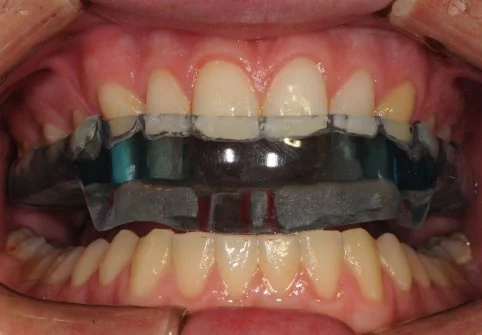

A TMJ Disorder patient requires conservative management with “Full Occlusal Therapy” in 3 stages along with concurrent Full Counselling (refer to journal papers 19 and 20).  In other words, we need to get the disc back into the centre of the joint where it belongs starting with Full Counselling and then a Fully Protective Occlusal Splint (Stage 1).  This splint is made of acrylic resin (used for dentures) and can be made in clear resin but is usually coloured blue or pink to hide any future discolouration (as in the photos below). The splint usually fits the upper teeth and only one is required.

Stage 1 - Fully Protective Occlusal Splint - 4 SA’s over a 3 month period

Stage 1 of Full Occlusal Therapy is Formal Fully Protective Occlusal Splint Therapy with case study